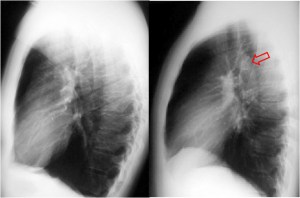

SIGNO DEL CASQUETE APICAL IZQUIERDO

La aparición de una densidad en el ápex pulmonar izquierdo, de borde inferior cóncavo y bien delimitado (casquete apical) en un paciente con traumatismo torácico, debe hacernos sospechar la existencia de una rotura aórtica.

Deben excluirse otras causas de casquete apical, especialmente las lesiones residuales tuberculosas, que suelen acompañarse de otros hallazgos como tractos fibrosos pleuro-parenquimatosos, pérdida de volumen en el lóbulo superior, granulomas, etc.

Mostramos un caso de rotura aórtica por accidente de moto. En este paciente también aparece el signo de la alteración del contorno aórtico.

En la radiografía lateral de tórax, se ha descrito que la ausencia de la imagen del arco aórtico puede ser la clave diagnóstica de coartación aórtica. La imagen izquierda muestra el signo. Se trata del mismo paciente del Signo de las muescas costales (ver Otros signos de pleura/pared). La imagen derecha corresponde a una radiografía normal con la sombra aórtica visible (flecha).

Se han propuesto varias explicaciones para este signo; puede ser debido a hipoplasia del arco aórtico combinada con la coartación, a dilatación de las arterias braquiocefálicas (particularmente la arteria subclavia izquierda) que oscurecen el margen superior del cayado, o a hipoplasia y desplazamiento anteromedial de la porción distal del arco aórtico.